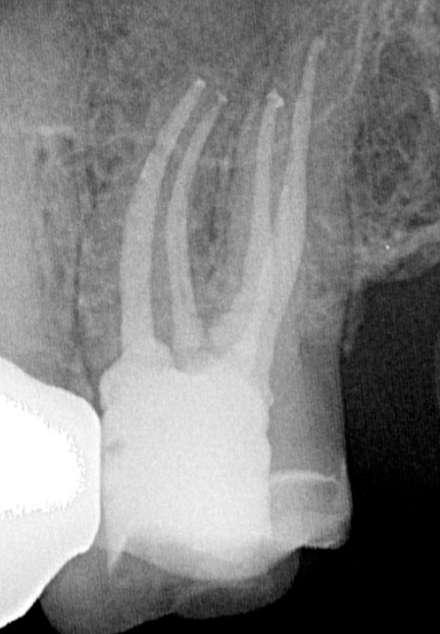

Die endodontische Behandlung fand in einer Sitzung statt. Nach Anästhesie und Anlegen des Kofferdams erfolgte die Entfernung der provisorischen Füllung und die initiale intrakoronale Diagnostik. Mittels Microopener konnte ein mesiobukkaler, mesiolingualer, distobukkaler und distolingualer Wurzelkanal sondiert werden. Die Ausarbeitung der primären Zugangskavität zur besseren Zugänglichkeit der Kanäle erfolgte mit Langschaftrosenbohrern. Anhand des präoperativen diagnostischen Röntgenbilds konnte die Länge der Wurzelkanäle vorläufig näherungsweise bestimmt werden. Die Kanäle wurden im weiteren Therapieverlauf kontinuierlich mit 6% NaOCl gespült. Nach Ausarbeitung der Zugangskavität folgte die koronale Erweiterung der Wurzelkanäle mit EdgeEndo X7 Feilen der Größe 17.06. Die elektrometrische Bestimmung der Kanallänge mithilfe eines Morita Root ZX Mini Apex Locators wurde mit C-Piloten der Größe 8-10 durchgeführt. Nach Festlegung der Arbeitslänge wurde der

Gleitpfad rotierend mit EdgeFile X7 der Größe 17.04 und 25.04 erweitert und final bis auf 30.04 aufbereitet (Abbildung 2).

Abbildung 2: Blick auf das mesiale Kanalsystem nach Präparation